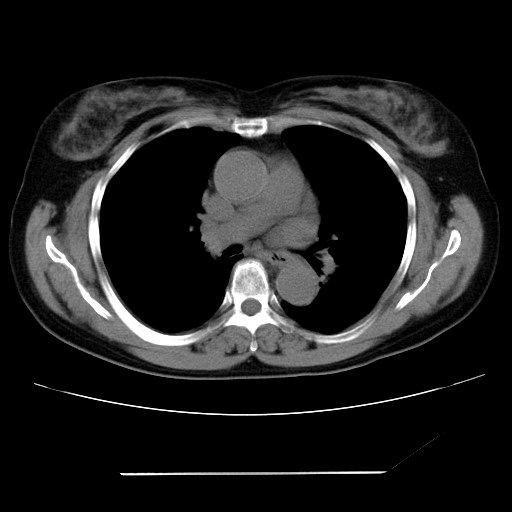

标题: CT24018:女性,62岁,咳嗽4年,无热,胸部CT扫 [打印本页]

女性,62岁,长期咳嗽,既往从事工作有粉尘接触,有高血压病史,110/150mmhg,近日咳嗽加重,脸面浮肿,请大家帮看下,

1、尘肺;2、慢性支气管炎合并肺部感染;3、心影增大(左房、左室大),考虑高血压性心脏病。

慢支并肺部炎症;右肺结核球?主肺动脉、右肺动脉影不宽,右心室不大,不支持肺心病;无心包积液。

1)慢性支气管炎并肺部感染、肺气肿。2)肺间质纤维化。

间质性肺炎,左下肺机化性肺炎。